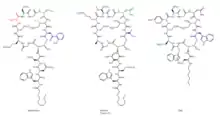

The molecular engineering of daptomycin, the only marketed acidic lipopeptide antibiotic to date (Figure 8), has seen many advances since its inception into clinical medicine in 2003.[34] It is an attractive target for combinatorial biosynthesis for many reasons: second generation derivatives are currently in the clinic for development;[35] Streptomyces roseosporus, the producer organism of daptomycin, is amenable to genetic manipulation;[36] the daptomycin biosynthetic gene cluster has been cloned, sequenced, and expressed in S. lividans;[35] the lipopeptide biosynthetic machinery has the potential to be interrupted by variations of natural precursors, as well as precursor-directed biosynthesis, gene deletion, genetic exchange, and module exchange;[36] the molecular engineering tools have been developed to facilitate the expression of the three individual NRPS genes from three different sites in the chromosome, using ermEp* for expression of two genes from ectopic loci;[37] other lipopeptide gene clusters, both related and unrelated to daptomycin, have been cloned and sequenced,[29] thus providing genes and modules to allow the generation of hybrid molecules;[36] derivatives can be afforded via chemoenzymatic synthesis;[38] and lastly, efforts in medicinal chemistry are able to further modify these products of molecular engineering.[35]

New derivatives of daptomycin (Figure 9) were originally generated by exchanging the third NRPS subunit (dptD) with the terminal subunits from the A54145 (Factor B1) or calcium-dependent antibiotic pathways to create molecules containing Trp13, Ile13, or Val13.[39] dptD is responsible for incorporating the penultimate amino acid, 3-methyl-glutamic acid (3mGlu12), and the last amino acid, Kyn13, into the chain. This exchange was achieved without engineering the interpeptide docking sites. These whole-subunit exchanges have been coupled with the deletion of the Glu12-methyltransferase gene, with module exchanges at intradomain linker sites at Ala8 and Ser11, and with variations of natural fatty-acid side chains to generate over 70 novel lipopeptides in significant quantities; most of these resultant lipopeptides have potent antibacterial activities.[29][39] Some of these compounds have in vitro antibacterial activities analogous to daptomycin. Further, one displayed ameliorated activity against an E. coli imp mutant that was defective in its ability to assemble its inherent lipopolysaccharide. A number of these compounds were produced in yields that spanned from 100 to 250 mg/liter; this, of course, opens up the possibility for successful scale-ups by fermentation techniques. Only a small percentage of the possible combinations of amino acids within the peptide core have been investigated thus far.[40]